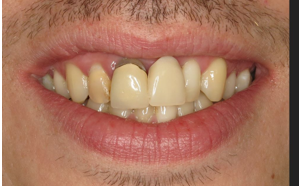

Before And After

The patient has a high lip line and aesthetic outcome was important